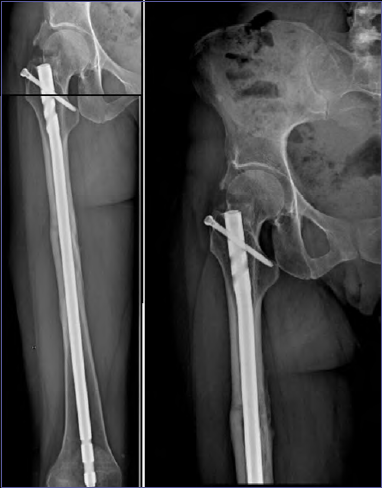

Patients with a galeazzi fracture, a pathological fracture, or patients with nonunion after previous surgeries were excluded. 10 year old boy with transverse fracture of the diaphysis midshaft.

COMPRESSION PLATING OF ACUTE FEMORAL SHAFT FRACTURES

COMPRESSION PLATING OF ACUTE FEMORAL SHAFT FRACTURES from m3.healio.com